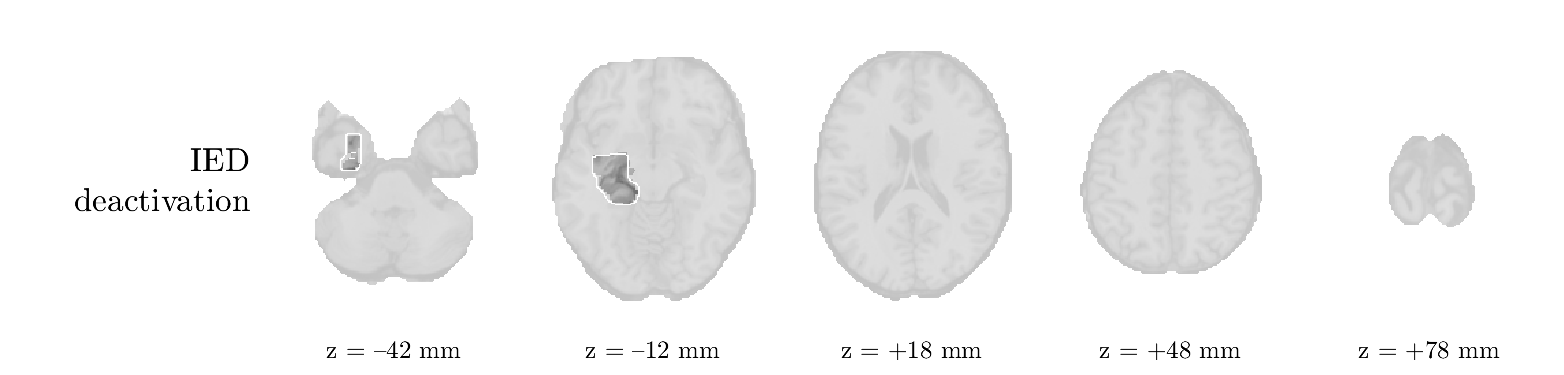

Patient 2

We analyze the solution with sources, and show the results in Figure 3 and 4. As for patient 1, we found a source which is strongly correlated to the MWF envelope, and which had a mostly low-frequency behavior characteristic for spikes. The topography is mostly uninformative, and does not clearly correspond to the patient’s clinical data. The third source is mostly present at both sides of the head, is very sparsely active in time, and has a high-frequency content: this is most likely an artifact due to the neck muscles. Again, there is one of the highest-entropy HRFs which belongs to a ROI in the IOZ. Now, the waveform is clearly resolved from the other HRFs, through the strong initial dip (before 0 seconds). Such a dip is sometimes observed in HRFs, but its underlying physiological mechanism is not yet fully understood. It is possible that this dip reflects altered vascular autoregulation near the IOZ (cfr. the explanation in the Section 1 of the main text), or a rapid depletion in oxygen due to IED generation (before the IED becomes visible on the EEG). Figure 4 furthermore shows that the IED-related component is significantly active in parts of the IOZ, and deactive in others. As mentioned earlier, this deactivation may or may not be due to errors in sign correction. Interestingly, the ROI with the high alteration in neurovascular coupling is distinct from both the activated and deactivated ROIs.